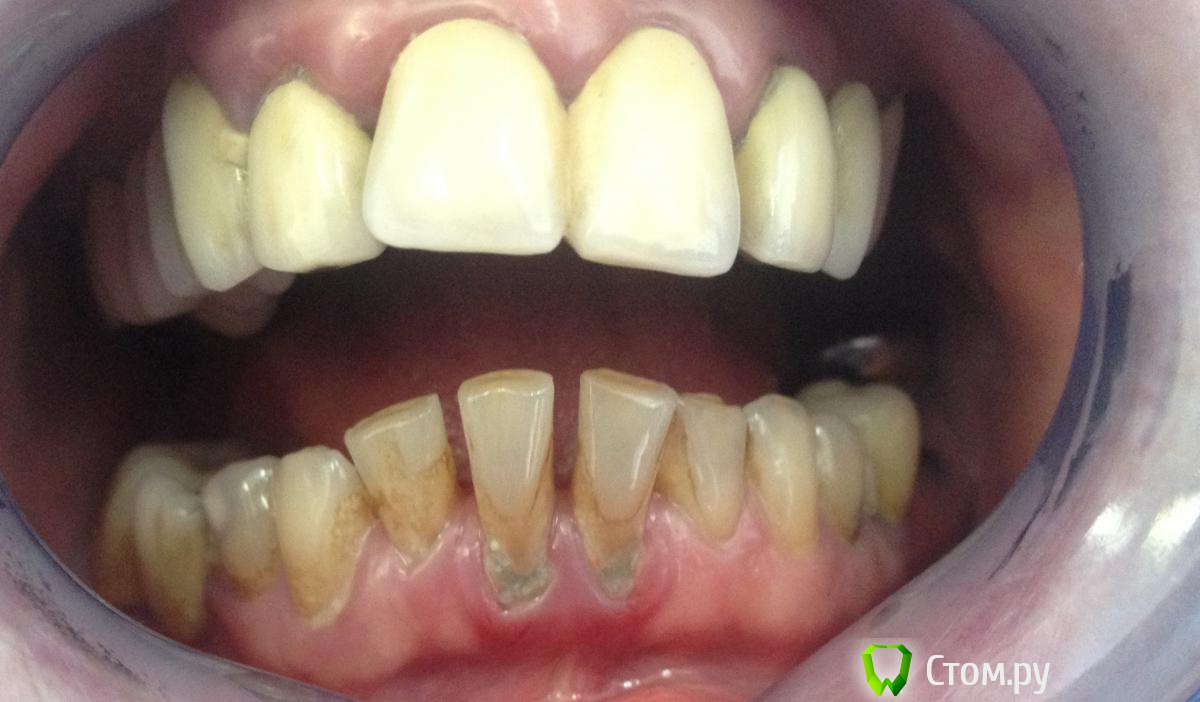

MaxDok Опубликовано 31 января, 2014 Поделиться Опубликовано 31 января, 2014 Пациент, 45 лет. Жалобы на эстетически не состояельные реставрации . Хочет красивую улыбку С чего посоветуете начать коллеги? Ссылка на комментарий

MaxDok Опубликовано 31 января, 2014 Автор Поделиться Опубликовано 31 января, 2014 (изменено) Разговаривал, ортодонтическое лечение говорит было,но НЕ удачно.Пациент адекватный , понимает что голивуд не получится.wax-up будет только в пятницу готов . Изменено 31 января, 2014 пользователем MaxDok Ссылка на комментарий

scarifikator Опубликовано 31 января, 2014 Поделиться Опубликовано 31 января, 2014 Если пациент адекватный и понимает тяжесть своей ситуации, понимает что изменения будут носить косметический, а не радикальный характер (ибо без ортодонтии как минимум ничего тут не поправиться) и при одобрении со стороны пациента плана и методов протезирования, снял бы мосты, провел хир- и тер-подготовку, с имплантологом окончательно спланировал места установки имплантатов, провел финальную презентацию в полости рта и... в путь Ссылка на комментарий

MaxDok Опубликовано 31 января, 2014 Автор Поделиться Опубликовано 31 января, 2014 В моем городе врятли кто из ортодонтов ( а их можно по пальцам одной руки пересчитать ) возьмется . В другой город лететь соглашаются единицы , дороговато с Камчатки это делать . Интересно какая окклюзиционная схема получится. и жизнеспособность всего этого без ортодонтии. Ссылка на комментарий

Lolopop Опубликовано 16 марта, 2014 Поделиться Опубликовано 16 марта, 2014 как же я вас понимаю...вам повезло что у вас пациентка адекватная, была у меня очень похожая с вашей, такой же глубокий прикус, без адекватный дистальных опор, все склонял к ортодонтии с имплантацией, даже начал все снимать, но пациентка перед терапевтической санации просто пропала.. Ссылка на комментарий